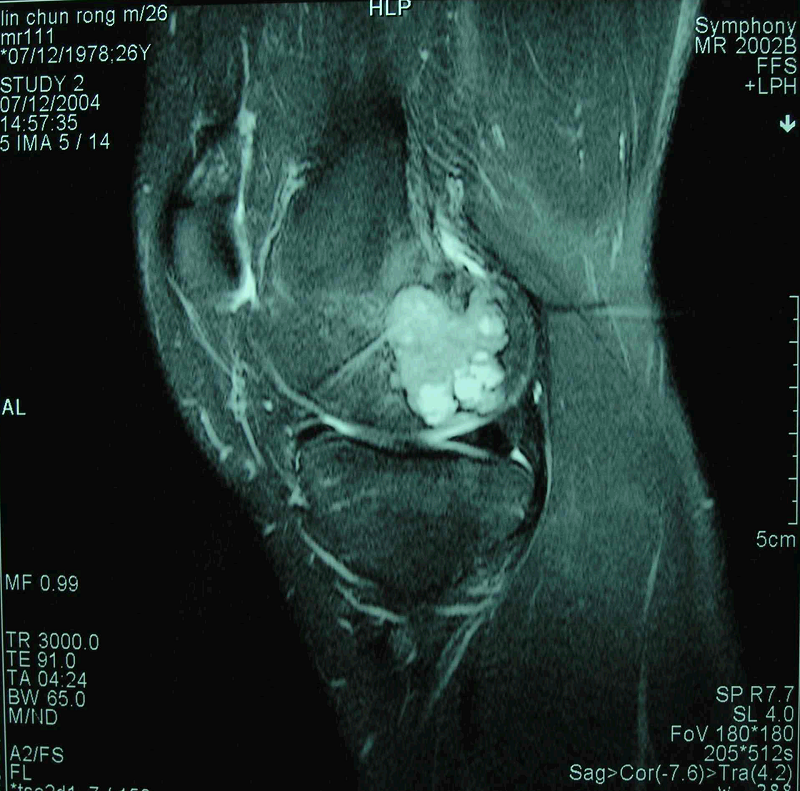

患者 男 26岁 左股骨下端骨母细胞瘤

图 3 术前MRI-T2WI